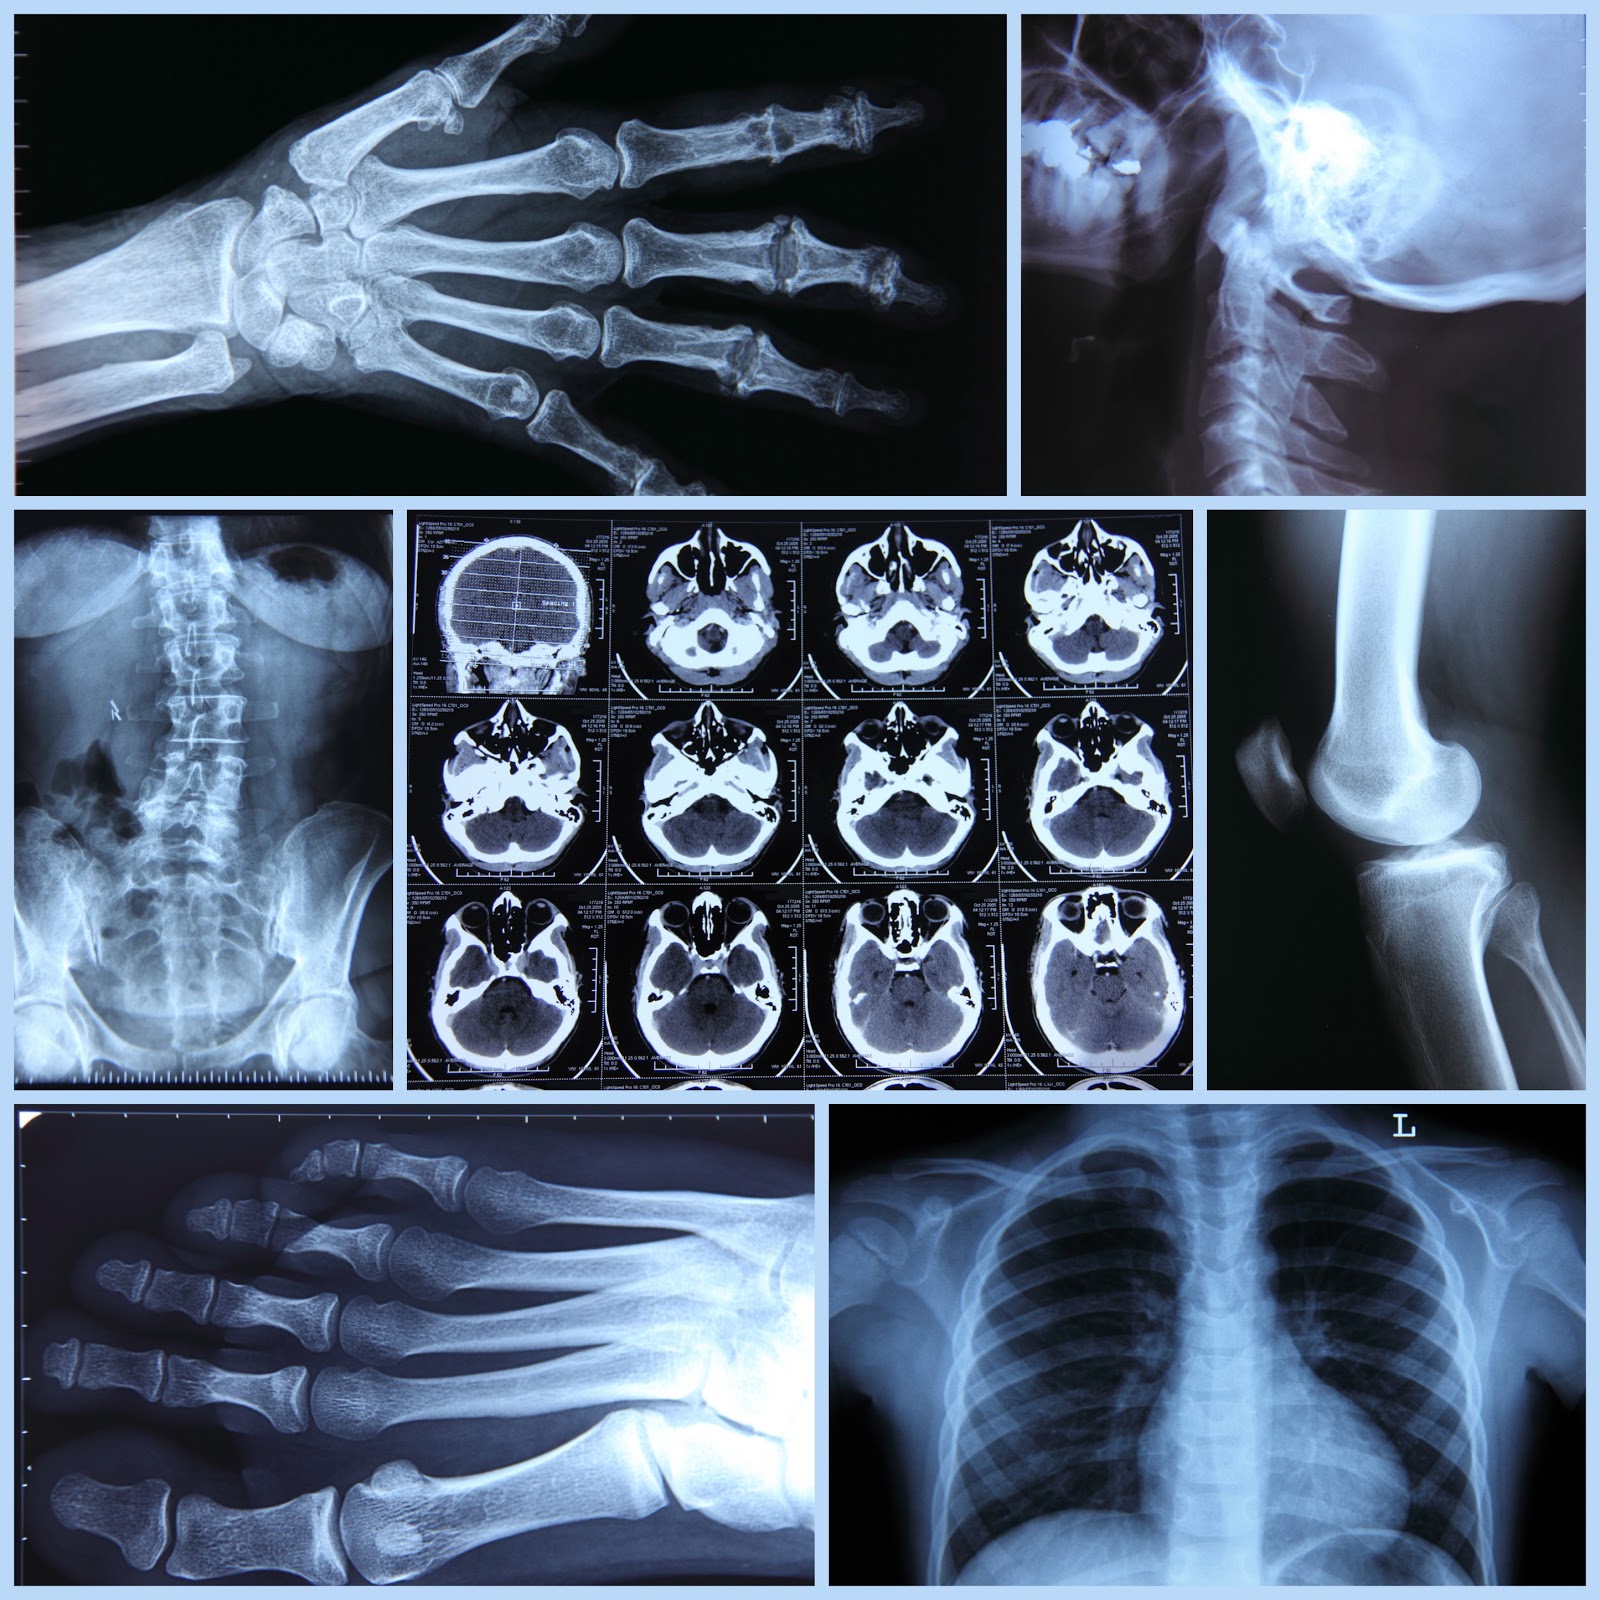

La tomografía computarizada emplea rayos X para generar imágenes transversales del cuerpo, proporcionando una visión más detallada que una radiografía convencional. El escáner gira alrededor del paciente y captura múltiples imágenes que son procesadas por una computadora para reconstruir una representación tridimensional de los órganos y tejidos internos. Este procedimiento es fundamental en el diagnóstico de enfermedades neurológicas, cardiovasculares, oncológicas y traumatológicas.

Uno de los principales cuestionamientos sobre la tomografía computarizada es la cantidad de radiación a la que se expone el paciente. A diferencia de una radiografía convencional, una tomografía emite dosis más altas de radiación debido a la cantidad de imágenes que se generan en un solo estudio. Sin embargo, los niveles utilizados en la práctica clínica están regulados y optimizados para minimizar los efectos adversos.